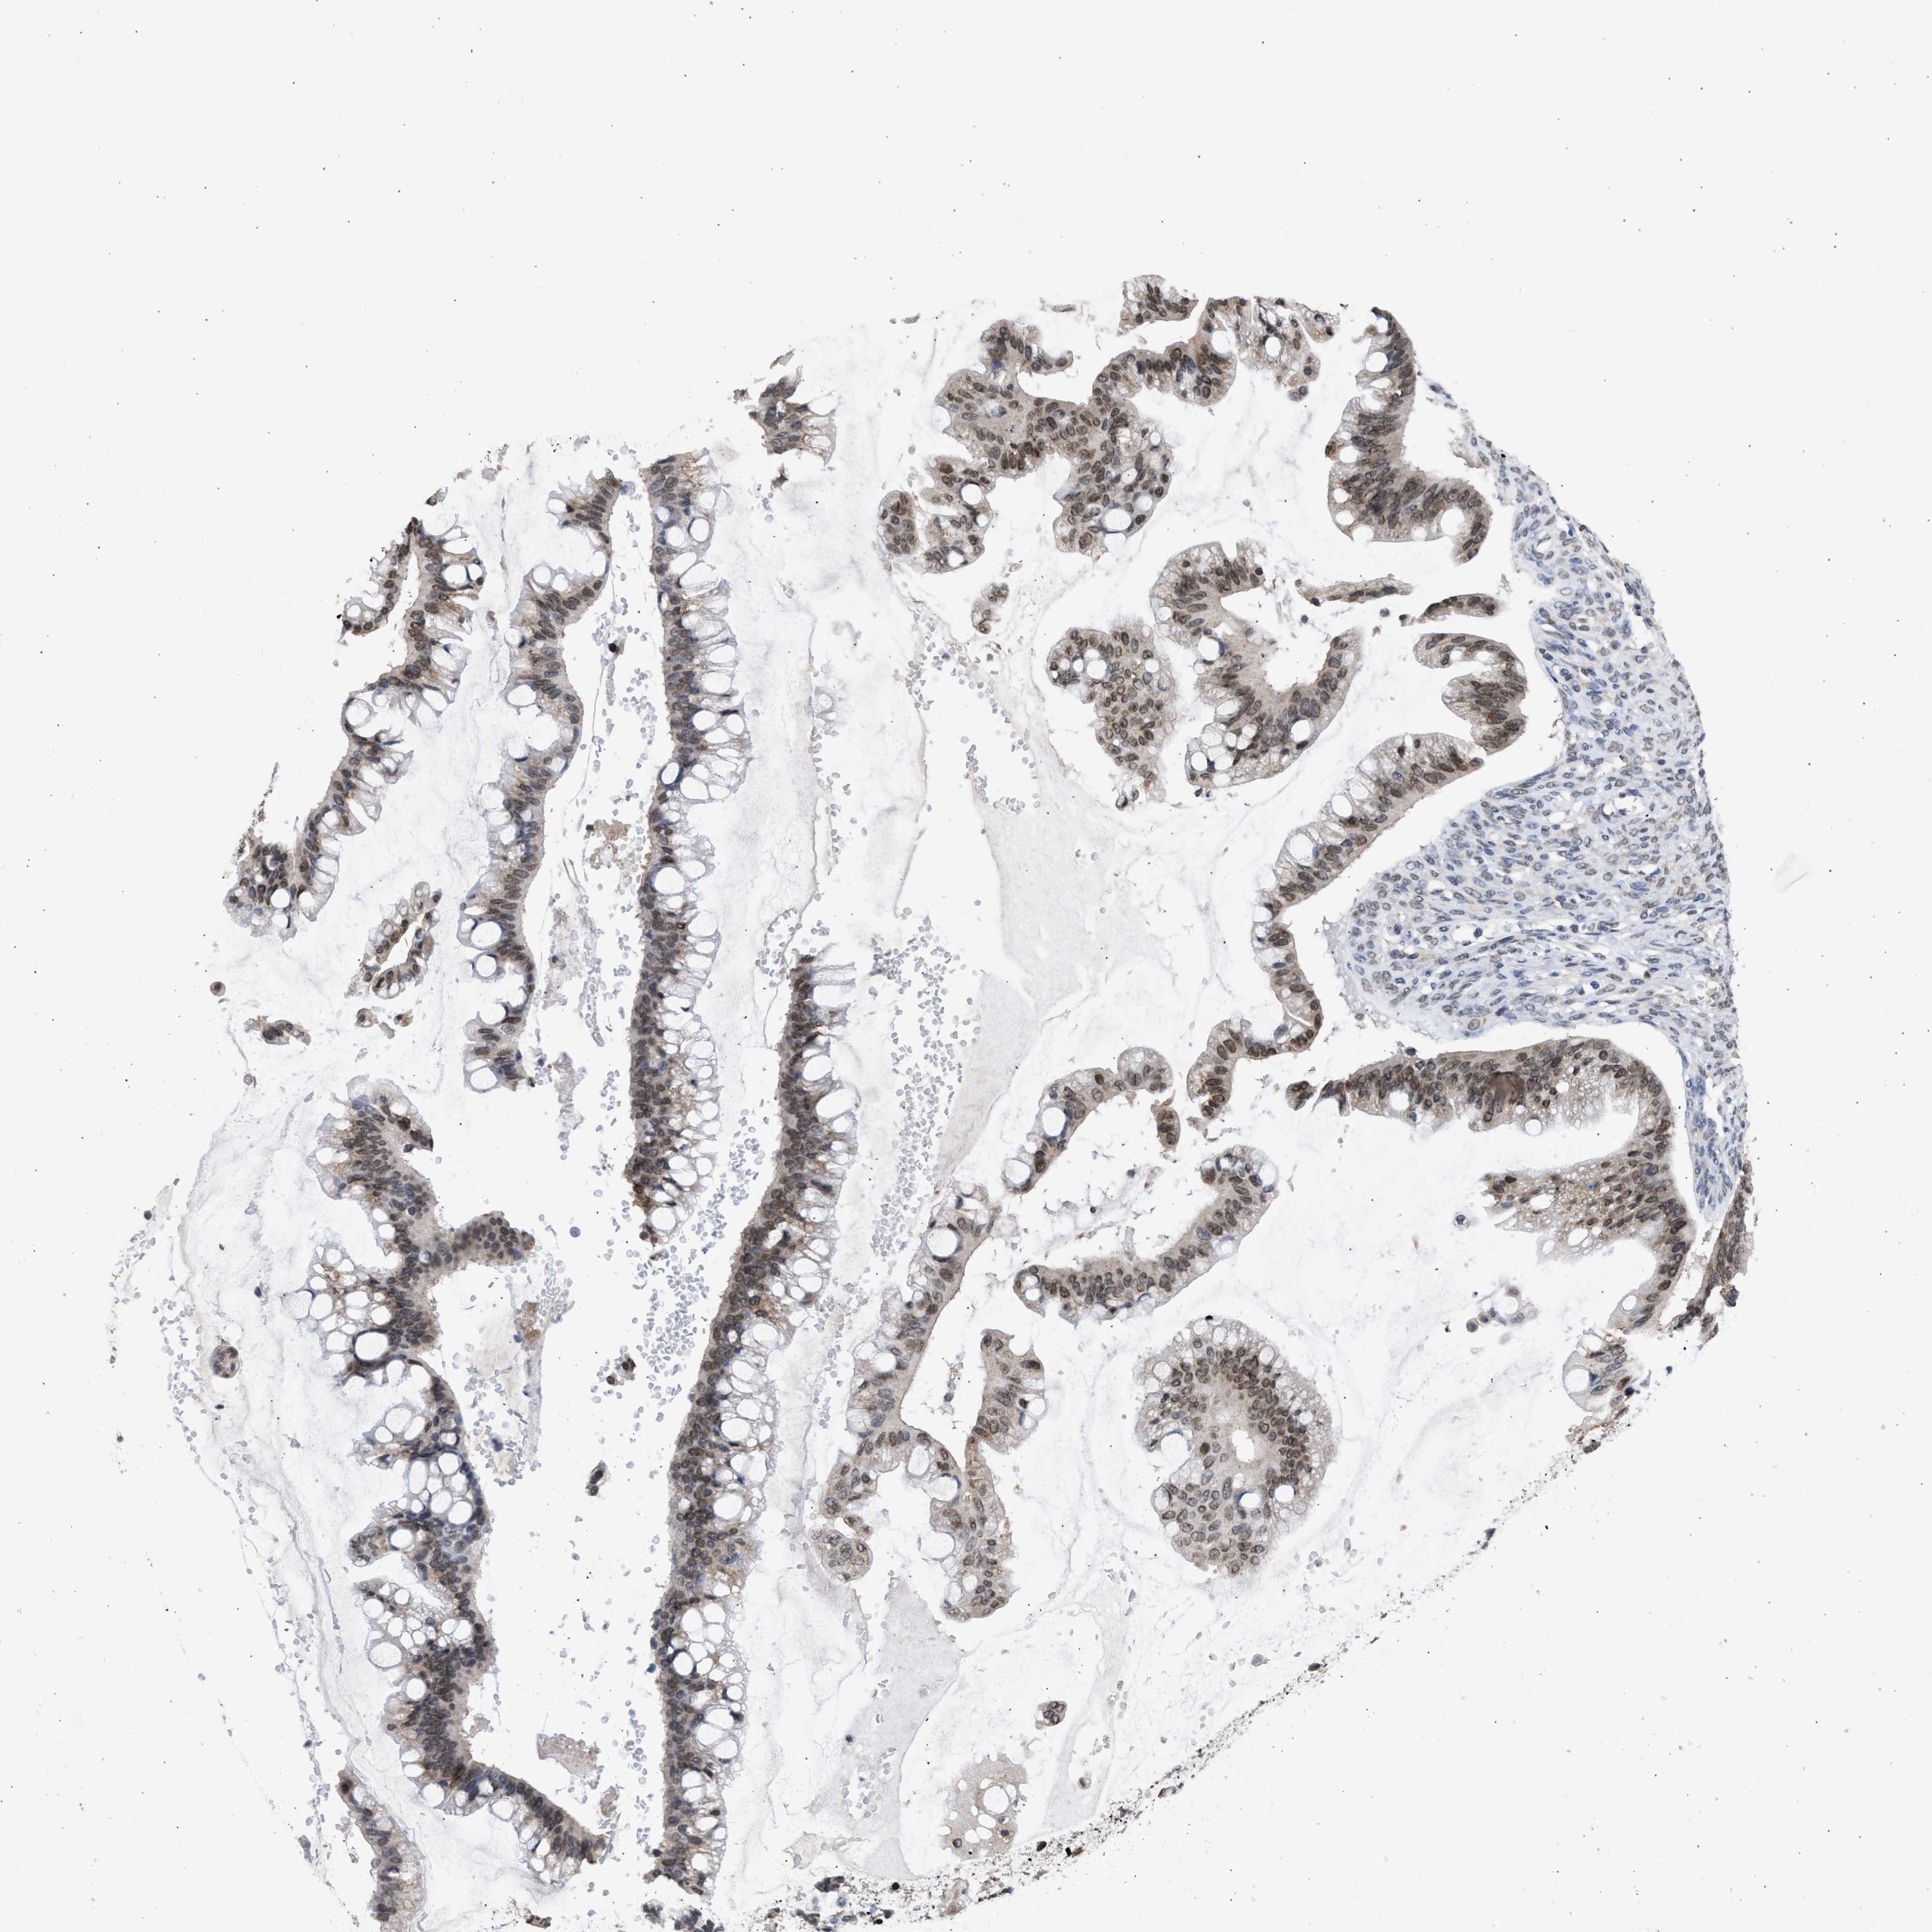

OVARIAN CANCER - Protein expressioni

A mouse-over function shows sample information and annotation data. Click on an image to view it in a full screen mode. Samples can be filtered based on level of antibody staining by selecting one or several of the following categories: high, medium, low and not detected. The assay and annotation is described here.

Note that samples used for immunohistochemistry by the Human Protein Atlas do not correspond to samples in the TCGA dataset.

Antibody stainingi

Antibody staining in the annotated cell types in the current human tissue is reported as not detected, low, medium, or high, based on conventional immunohistochemistry profiling in selected tissues. This score is based on the combination of the staining intensity and fraction of stained cells.

Each image is clickable and will lead to virtual microscopy that enables deeper exploration of all samples and also displays staining intensity scores, fraction scores and subcellular localization as well as patient and tissue information for each sample.

Antibody HPA018401

Antibody HPA018410

Antibody HPA018441

Staining

High

Medium

Low

Not detected

Intensity

Strong

Moderate

Weak

Negative

Quantity

>75%

75%-25%

<25%

None

Location

Nuclear

Cytoplasmic/membranous

Cytoplasmic/membranous,nuclear

Cystadenocarcinoma, serous, NOS

Carcinoma, endometroid

Cystadenocarcinoma, mucinous, NOS

Carcinoma, NOS